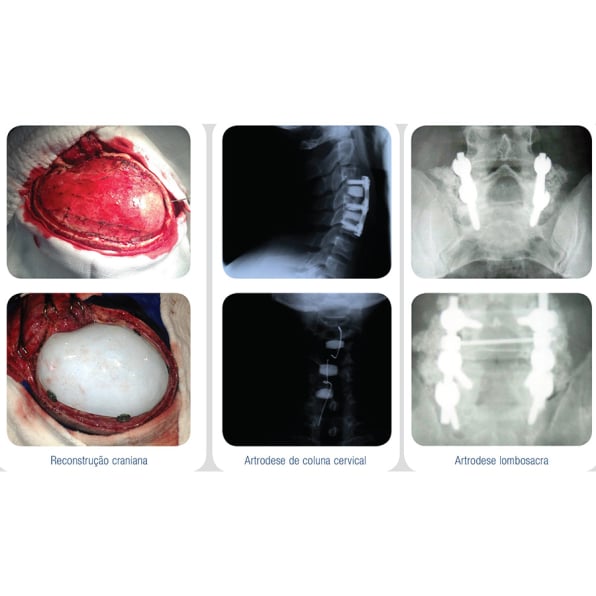

Na face e ossos do crânio, a maior indicação é a utilização de peças pré-moldadas individualmente conforme a necessidade do paciente para a reconstituição tecidual óssea.

Além do tratamento corretivo, esta técnica serve também como recurso estético anatômico, obedecendo os princípios da bioarquitetura, com perfeita soldadura com a estrutura óssea adjacente.

Na Neurocirurgia, as biossoluções EincoBio são utilizadas em casos como:

• Cranioplastias adulto, inclusive de grande dimensão;

• Cranioplastias pediátricas (acompanhando o crescimento do crânio);

• Reconstruções faciais e de crânio em geral;

• Tumores e artrodeses de coluna.